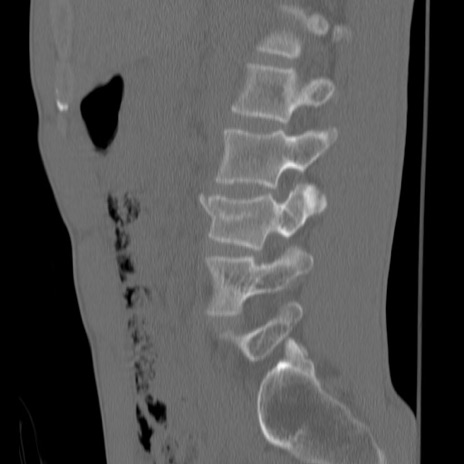

症例3 腰椎CT(矢状断像)

腰椎CT